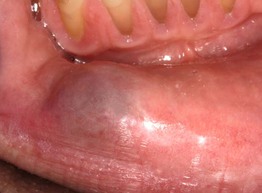

• Translucent to bluish papule due to disruption of a minor salivary gland duct, most often located on the lower mucosal lip (Fig. 59.8; see Chapter 90).

Fig. 59.8 Mucocele. Soft nodule with bluish hue in a typical location: lower lateral labial mucosa. Courtesy, Carl M. Allen, MD, and Charles Camisa, MD.